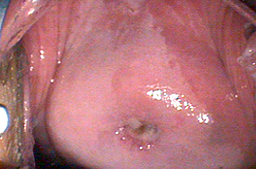

Cicatriazación al mes del tratamiento

• Cicatrización al sexto mes del tratamiento

Cicatrización al mes del tratamiento y cicatrización al sexto mes del tratamiento